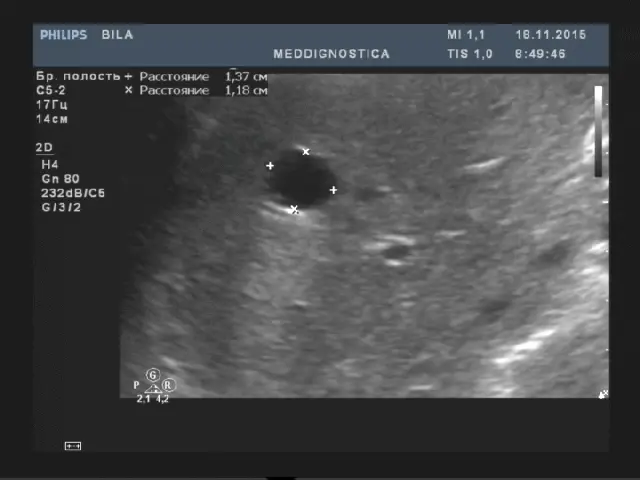

Товщина правої частки до 12.5см, товщина лівої частки до 6 см, товщина хвостатої частки до 3 см. Край лівої частки гострий. Поверхня гладка, ехогенність паренхіми середня, однорідна, звукопровідність не змінена. Капсула печінки чітко диференціюється. Судинний малюнок не змінений, не деформований. Воротна вена діаметром до 13мм, гілки ворітної вени: стіни не ущільнені, хід не деформований. Нижня порожниста вена не розширена, діаметр до 25мм. Холедоха діаметром до 7 мм. Лімфовузли воріт печінки не візуалізуються.

- об’ємні утворення (кісти, гемангіоми, пухлини, метастази і ін.);